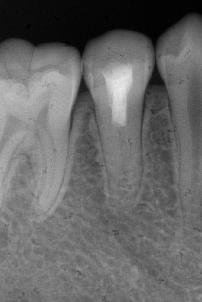

术后6个月